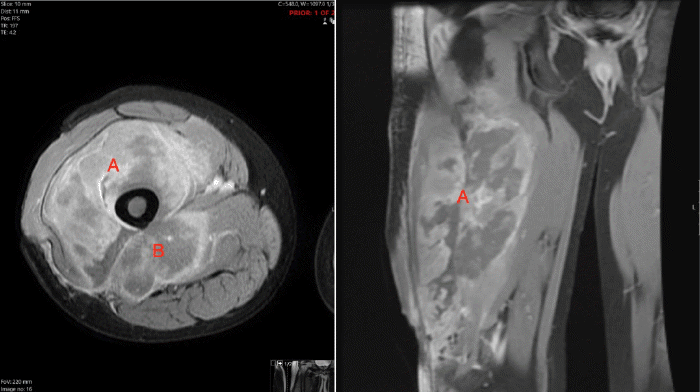

In the postoperative period, a comprehensive review of systems, facilitated by a licensed Spanish interpreter, revealed headaches, weight loss, and night sweats. MRI of the right thigh demonstrated a large, infiltrative mass originating from the right femoral shaft and extending into the anterior and posterior thigh compartments (Figure 2). Right inguinal adenopathy, small bony lesions of the femoral neck and posterior acetabulum, and abnormal marrow signal throughout the right femoral shaft were also noted. Staging CT and PET scans revealed a large heterogeneous mass in the right thigh, extending into the distal femur and knee joint, with bulky lymphadenopathy and heterogeneous mixed lytic and sclerotic changes of the right humerus, exhibiting intense fluorodeoxyglucose (FDG) uptake (Figure 3).

Figure 2. MRI of Right Thigh Demonstrating Infiltrative Mass. Published with Permission

Axial and coronal T2-weighted magnetic resonance imaging of the right thigh revealing a large, infiltrative mass originating from the right femoral shaft and extending into the (A) anterior and (B) posterior thigh compartments